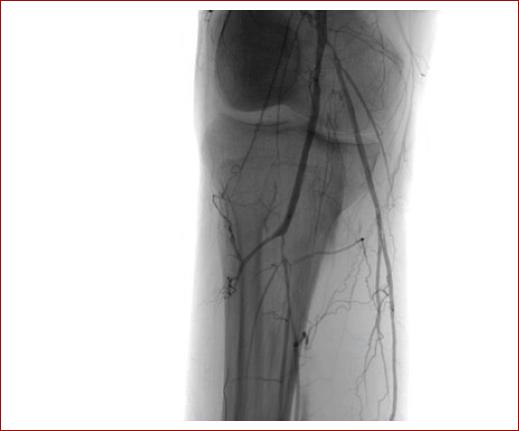

Utilizando guía hidrofílica 0.014 y catéter de soporte, se exploró la arteria tibial anterior, sin lograr franquear oclusiones hasta el pie. Se realizaron intentos no exitosos de acceso retrógrado ecoguiado pedio y tibial posterior. Finalmente, se decide realizar angioplastia simple de la arteria tibial anterior y de la arteria poplítea. Se realiza angiografía de control, en la que se verifica reclutamiento de colaterales previamente no observadas (Fig. 4) y se detecta disección segmentaria de la arteria poplítea y tronco tibioperoneo no limitante de flujo.

Figura 4 Recanalización de la arteria poplítea, con recoil de su porción proximal y estenosis residual significativa del tronco tibioperoneo. Abundante reclutamiento de colaterales.